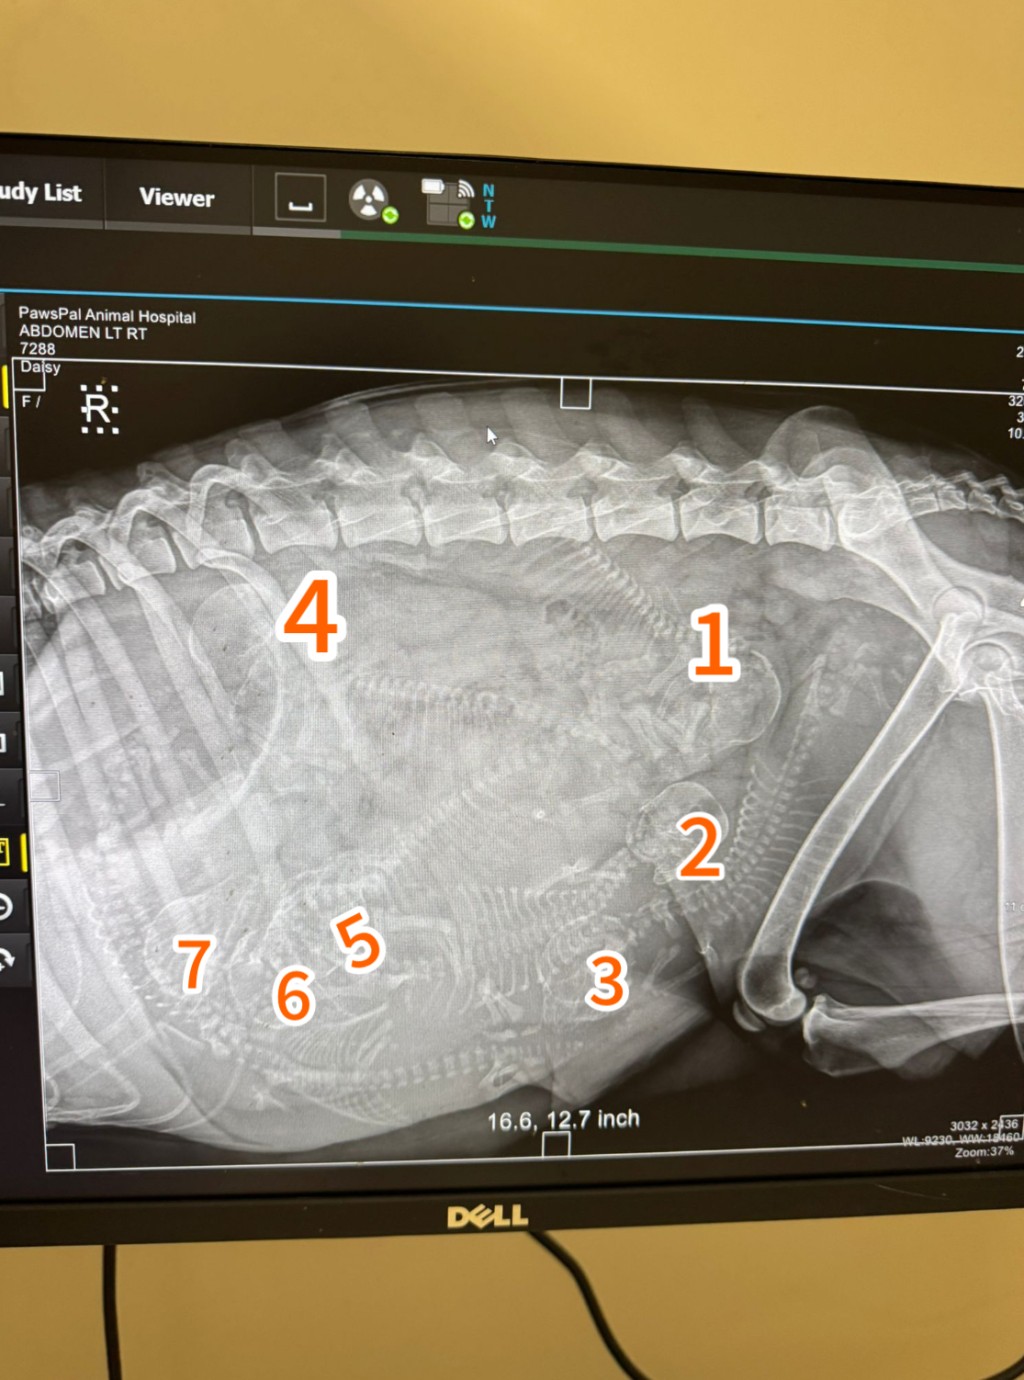

獸醫為牠進行檢查,驗血發現牠有貧血,而且已經懷孕,從X光中可以清楚見到有6個已經發育成形的寶寶,估計寶寶在這個星期內便會出生。

Angela媽媽說當獸醫照到狗狗肚內有7個BB時,她的情是又驚又喜,驚的是那麼瘦弱的狗狗要做媽媽,喜的是BB們仍有心跳,正努力求助。Angela説:「我𪊴幸可以及時救到她出來。」